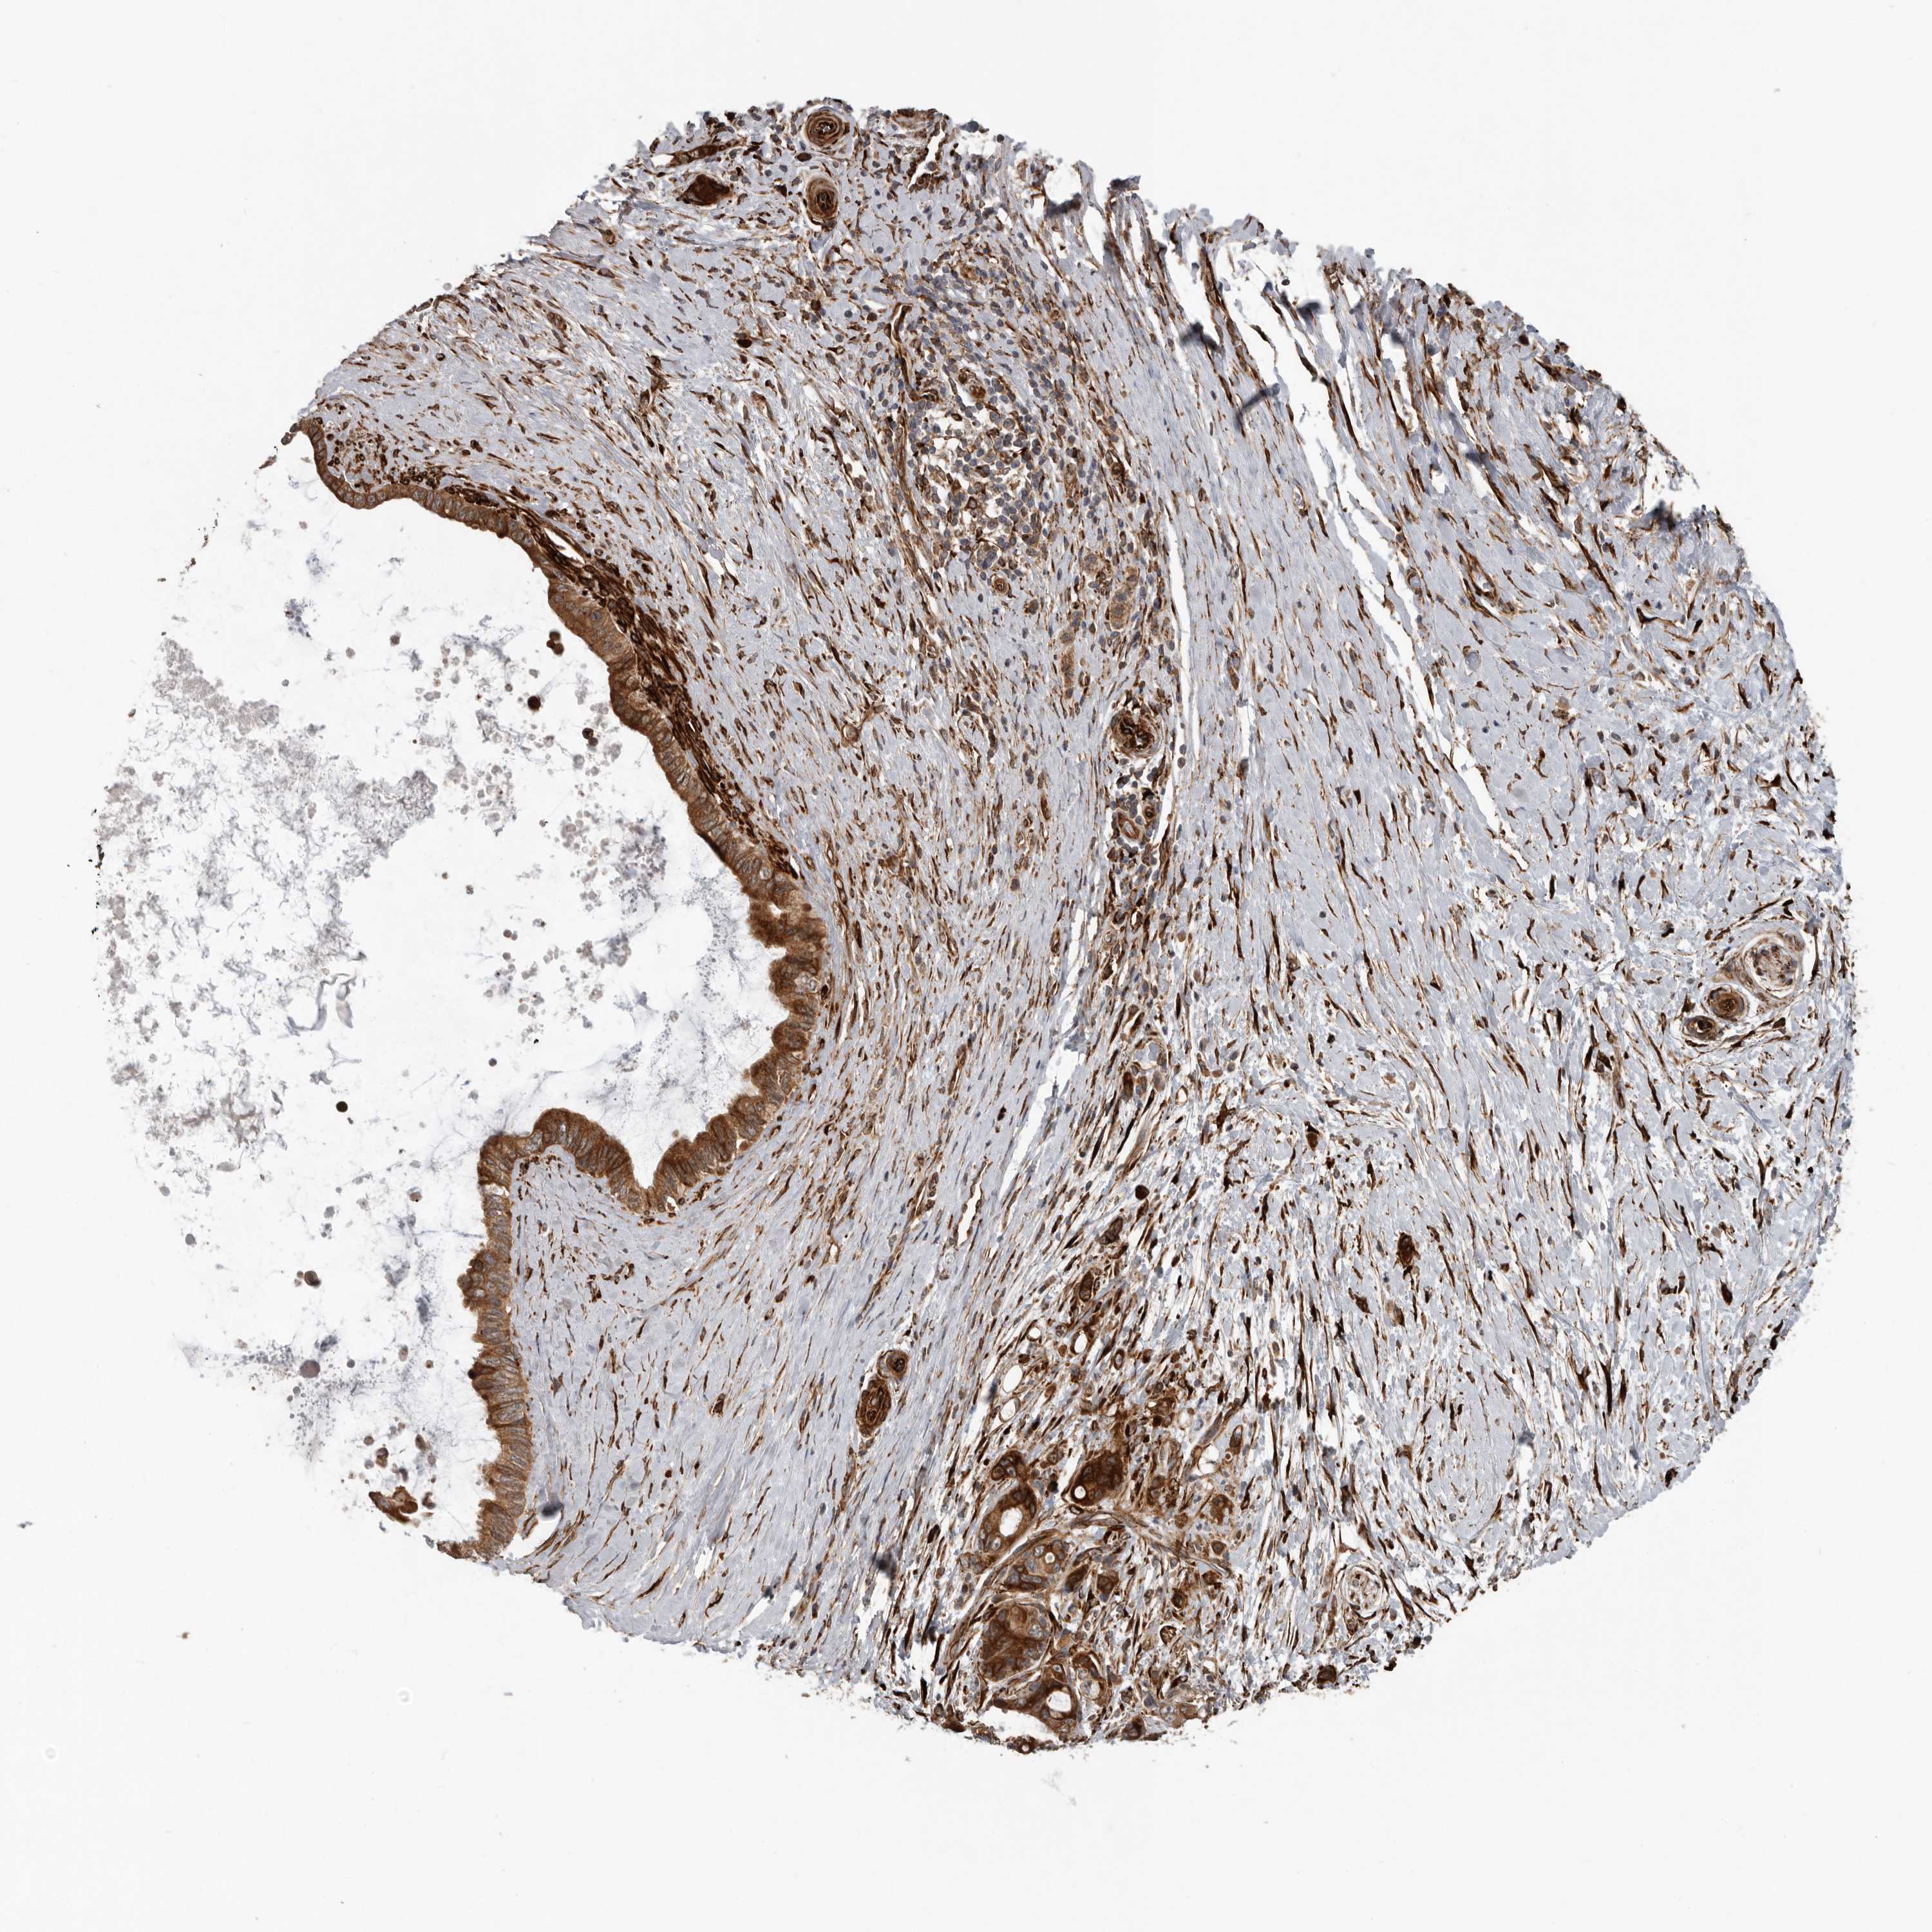

PANCREATIC CANCER - Protein expressioni

A mouse-over function shows sample information and annotation data. Click on an image to view it in a full screen mode. Samples can be filtered based on level of antibody staining by selecting one or several of the following categories: high, medium, low and not detected. The assay and annotation is described here.

Note that samples used for immunohistochemistry by the Human Protein Atlas do not correspond to samples in the TCGA dataset.

Antibody stainingi

Antibody staining in the annotated cell types in the current human tissue is reported as not detected, low, medium, or high, based on conventional immunohistochemistry profiling in selected tissues. This score is based on the combination of the staining intensity and fraction of stained cells.

Each image is clickable and will lead to virtual microscopy that enables deeper exploration of all samples and also displays staining intensity scores, fraction scores and subcellular localization as well as patient and tissue information for each sample.

Antibody HPA028355

Antibody HPA028357

Staining

High

Medium

Low

Not detected

Intensity

Strong

Moderate

Weak

Negative

Quantity

>75%

75%-25%

<25%

None

Location

Nuclear

Cytoplasmic/membranous

Cytoplasmic/membranous,nuclear

Adenocarcinoma, NOS